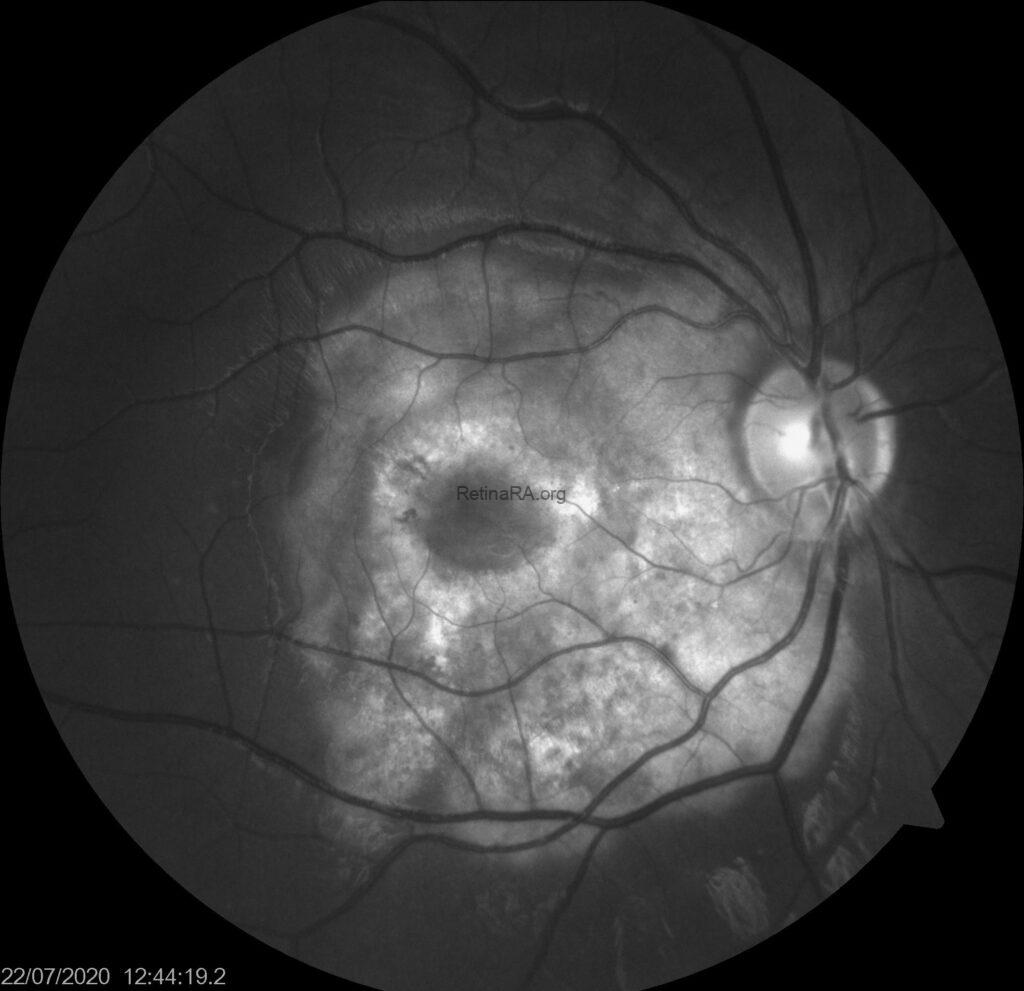

Fundus autofluorescence image demonstrated a mixed autofluorescence pattern. The central area appears hypoautofluorescent, suggestive of decalcification and retinal pigment epithelium atrophy. Surrounding this region, irregular zones of iso- to hyperautofluorescence reflect preserved or calcified segments of the lesion. The mottled autofluorescence is consistent with chronic remodeling of the lesion and may indicate areas at risk for functional deterioration.

Fundus fluorescein angiography showed a mottled pattern of hyper- and hypofluorescence corresponding to the calcified and decalcified portions of the lesion. Early-phase images show background choroidal filling with blocked fluorescence in areas of dense calcification. The central dark ring suggests decalcification and possible RPE atrophy, while focal late hyperfluorescence may represent window defects or early choroidal neovascularization. The lesion borders remain relatively well demarcated throughout the angiographic sequence.